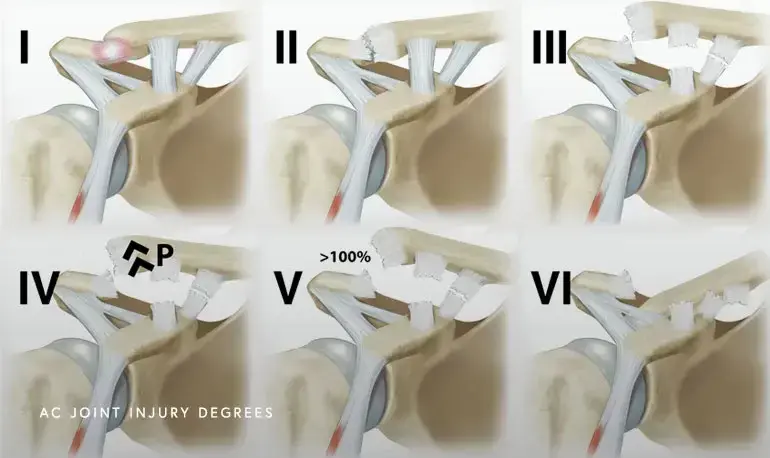

تتراوح شدة إصابات مفصل الترقوة الأخرمي من التواء بسيط في الأربطة إلى خلع كامل للمفصل. يتم تصنيف هذه الإصابات بشكل واسع باستخدام نظام تصنيف روكوود (Rockwood classification system)، والذي يقسم الإصابات إلى ستة أنواع بناءً على درجة تمزق الأربطة ومدى إزاحة عظم الترقوة بالنسبة للأخرم. هذا التصنيف يساعد الأطباء على تحديد خطة العلاج الأنسب لكل مريض.

تظهر إصابات مفصل الترقوة الأخرمي توزيعًا ذا نمطين عمريين: ذروة في الشباب النشطين والرياضيين، وذروة أخرى في كبار السن بسبب السقوط. بينما تستجيب إصابات النوع الأول والثاني غالبًا للعلاج غير الجراحي، تظل إصابات النوع الثالث مثيرة للجدل، أما إصابات النوع الرابع والخامس والسادس فتتطلب عادةً التدخل الجراحي نظرًا لعدم الاستقرار الكبير والتشوه التجميلي وضعف الوظيفة الذي تسببه.

النوع الأول:

التواء أربطة الترقوة الأخرمي، مع بقاء المحفظة سليمة.

النوع الثاني:

تمزق كامل لأربطة الترقوة الأخرمي والمحفظة، مع بقاء الأربطة الغرابية الترقوية سليمة. يسمح هذا بإزاحة طفيفة للترقوة للأعلى وعدم استقرار أمامي خلفي.

النوع الثالث:

تمزق كامل لكل من أربطة الترقوة الأخرمي والأربطة الغرابية الترقوية. يؤدي هذا إلى عدم استقرار عمودي كبير، وفقدان المحاذاة الطبيعية لمفصل الترقوة الأخرمي، وتمزق اللفافة الدالية شبه المنحرفة. تهاجر الترقوة للأعلى بسبب سحب العضلة القصية الترقوية الخشائية غير المعارض.

النوع الرابع والخامس والسادس:

تمثل هذه الأنواع شدة متزايدة لإصابات النوع الثالث مع متجهات إزاحة إضافية (خلفية داخل العضلة شبه المنحرفة، إزاحة علوية جسيمة مع تمزق واسع لللفافة، أو إزاحة سفلية).

يُعد تصنيف روكوود النظام الأكثر شيوعًا لتصنيف إصابات مفصل الترقوة الأخرمي، ويساعد في تحديد العلاج المناسب. يعتمد التصنيف على درجة تمزق الأربطة ومدى إزاحة الترقوة.

| النوع | وصف الإصابة | الأربطة المتأثرة | الإزاحة |

|---|---|---|---|

| النوع الأول (Type I) | التواء في أربطة الترقوة الأخرمي دون تمزق كامل؛ المفصل مستقر. | التواء في أربطة الترقوة الأخرمي | لا يوجد إزاحة |

| النوع الثاني (Type II) | تمزق كامل في أربطة الترقوة الأخرمي، لكن الأربطة الغرابية الترقوية سليمة؛ خلع علوي خفيف للترقوة. | تمزق كامل في أربطة الترقوة الأخرمي | إزاحة علوية خفيفة (<25% من المسافة الغرابية الترقوية) |

| النوع الثالث (Type III) | تمزق كامل لكل من أربطة الترقوة الأخرمي والأربطة الغرابية الترقوية؛ إزاحة واضحة للترقوة للأعلى. | تمزق كامل في أربطة الترقوة الأخرمي والأربطة الغرابية الترقوية | إزاحة علوية تتراوح بين 25-100% زيادة في المسافة الغرابية الترقوية |

| النوع الرابع (Type IV) | تمزق كامل في أربطة الترقوة الأخرمي والغربية الترقوية؛ إزاحة الترقوة خلفيًا داخل أو عبر العضلة شبه المنحرفة. | تمزق كامل في أربطة الترقوة الأخرمي والأربطة الغرابية الترقوية | إزاحة خلفية للترقوة |

| النوع الخامس (Type V) | تمزق كامل في أربطة الترقوة الأخرمي والغربية الترقوية، مع إزاحة علوية شديدة للترقوة، غالبًا ما تتجاوز 100% من المسافة الغرابية الترقوية، وانفصال اللفافة الدالية وشبه المنحرفة. | تمزق كامل وشديد في جميع الأربطة واللفافات المحيطة | إزاحة علوية شديدة (>100% من المسافة الغرابية الترقوية) |

| النوع السادس (Type VI) | نادر للغاية؛ تمزق كامل في أربطة الترقوة الأخرمي والغربية الترقوية مع إزاحة سفلية للترقوة تحت الناتئ الغرابي أو الأخرم. | تمزق كامل في جميع الأربطة | إزاحة سفلية للترقوة |